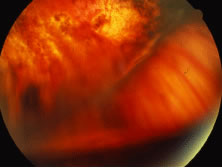

A variable number of eyes, up to 75%, develop retinal detachments (Fig. 5). Prophylactic laser for demarcating the areas of active retinitis from normal retina has been advocated to create chorioretinal adhesions that prevent retinal detachments around sites of retinal break formation (which usually occur at the zone between affected and healthy retina). Han and associates43 reported five cases treated with prophylactic laserpexy in addition to antiviral, steroid, and antiplatelet therapy. After 15 months of follow-up, no retinal detachments were noted. Sternberg and coworkers44 described a 75% decrease in the rate of retinal detachment using prophylactic photocoagulation. Some have advocated the creation of a “new ora serrata” by applying confluent rows of laser burns posterior to the areas of retinitis. However, if traction forces from vitreous organization, epiretinal membrane (ERM) formation, or proliferative vitreoretinopathy develop as they commonly do, the contractile forces will be able to overcome any increased chorioretinal adhesion created by the laserpexy. However, McDonald and associates45 reported failure of prophylactic peripheral laserpexy to prevent retinal detachment in ARN patients. In addition, many cases of ARN result in a severe vitritis, limiting the view for a planned laserpexy (Fig. 6). Therefore, vitrectomy with endolaser and concomitant encircling of the eye with a scleral buckle to reduce traction may be required in some patients.46,47 Decisions relating to the need for scleral buckling to support retinal breaks and the use of silicone oil or long-acting gases to repair retinal detachments should be made by an experienced vitreoretinal surgeon.40,48 Selection of cases to undergo operation should be made with consideration given to optic nerve function, visual potential, and medical control of retinitis.

Fig. 5. A patient with funnel-shaped retinal detachment and proliferative vitreoretinopathy complicating acute retinal necrosis syndrome.

Fig. 6. Failure of prophylactic laser treatment to stop the progression of a retinal detachment associated with retinal necrosis resulting from viral retinitis with progression of the detachment beyond the line of laser demarcation.